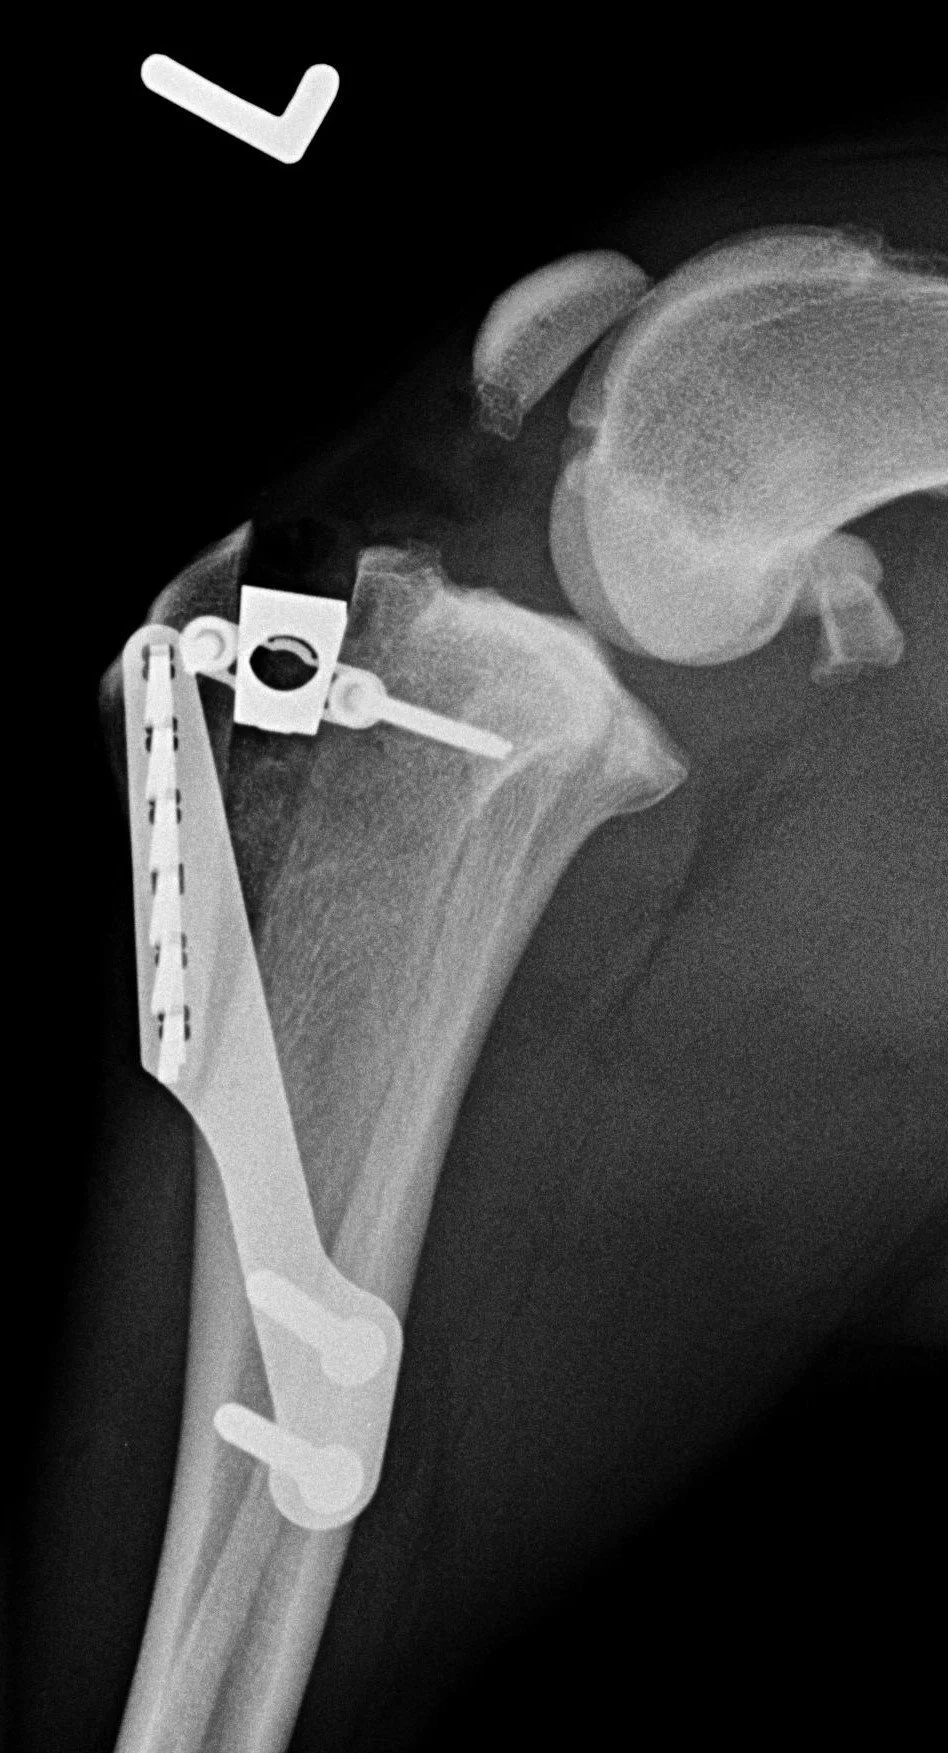

TTA bei Kreuzbandriss

Seit 2002 ist Dr. Reutter für das TTA Verfahren zeritifiziert (Kyon, CH). Unsere Praxis verfügt daher über die erforderliche langjährige Erfahrung zur Erzielung optimaler Ergebnisse in der chirurgischen Versorgung von Kreuzbandrupturen des Hundes und der Katze.

Die TTA (Tibial Tuberosity Advancement) ist eine moderne biomechanische Operationsmethode zur chirurgischen Versorgung von Kreuzbandrissen bei Hunden. Sie gilt als „state of the art" Methode, also das dem heutigen Stand der medizinischen Wissenschaft entsprechende Vorgehen

im Röntgenbild

Eingriff